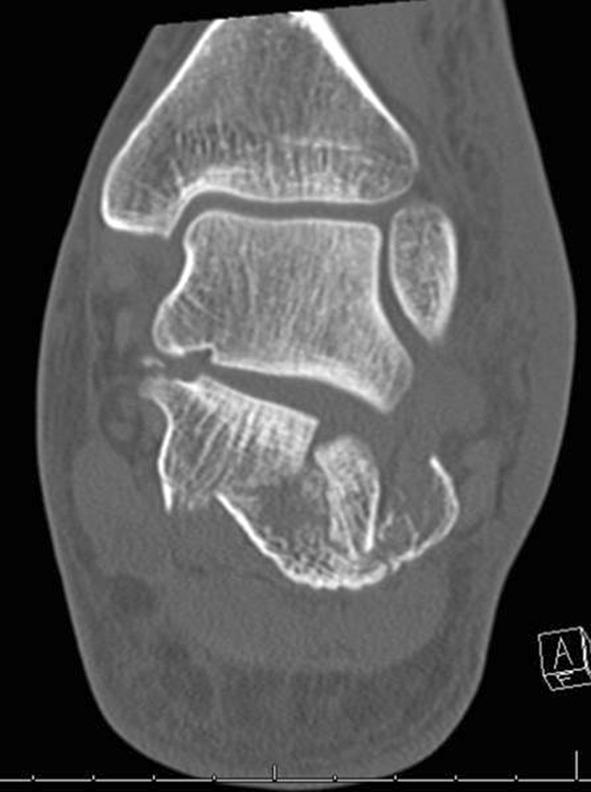

Calcaneal fractures: Where are we now?

This review article on the current management for calcaneal fractures discusses the advantages and disadvantages of different treatment options including the problems encountered. Controversies are described and the evidence reviewed. The management of some types of displaced intra-articular calcaneal fractures remains contentious; is there a preferred stabilisation method for each type of calcaneal fracture? How constant is the "constant fragment" in an intra-articular calcaneal fracture and what is the evidence for primary arthrodesis and what is its place in these fractures?